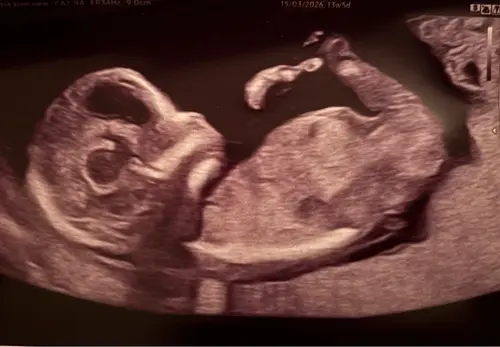

Weten jullie naar welke cirkel ik moet kijken? Dit is een 13,2 weken echo (tussen de beentjes) Bovenste lijken 2 streepjes van een meisje en daar onder lijkt een piemeltje.

Ik had bij mijn echo ook zo’n streep waardoor ik denk een jongen, maar als ik dan pottyshot foto’s zie van andere babies bij dezelfde termijn dan is het toch echt bij andere al beter te zien als het een jongen is.

Dus ik ben bang dat je nog een aantal weken moet wachten tot je zekerheid hebt 😅. Ga je een geslachtsbepalingsecho doen?